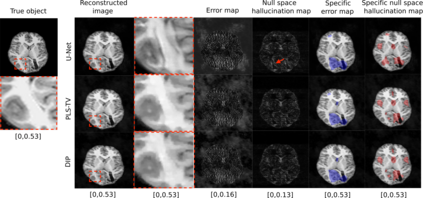

Tomographic image reconstruction is generally an ill-posed linear inverse problem. Such ill-posed inverse problems are typically regularized using prior knowledge of the sought-after object property. Recently, deep neural networks have been actively investigated for regularizing image reconstruction problems by learning a prior for the object properties from training images. However, an analysis of the prior information learned by these deep networks and their ability to generalize to data that may lie outside the training distribution is still being explored. An inaccurate prior might lead to false structures being hallucinated in the reconstructed image and that is a cause for serious concern in medical imaging. In this work, we propose to illustrate the effect of the prior imposed by a reconstruction method by decomposing the image estimate into generalized measurement and null components. The concept of a hallucination map is introduced for the general purpose of understanding the effect of the prior in regularized reconstruction methods. Numerical studies are conducted corresponding to a stylized tomographic imaging modality. The behavior of different reconstruction methods under the proposed formalism is discussed with the help of the numerical studies.

翻译:地形图象的重建一般是一个错误的线性反向问题,这种错误的反向问题通常利用事先对寻求的物体财产的了解加以规范化。最近,深神经网络通过从培训图像中学习物体属性的事先知识,积极调查使图像重建问题正规化;然而,对这些深网络所学的先前信息及其对可能存在于培训分发之外的数据进行概括化的能力的分析仍在探讨之中。以前不准确的情况可能导致在重建的图像中出现假结构,并引起医疗成像的严重关切。在这项工作中,我们提议通过将图像估计分解为一般测量和无效组成部分来说明重建方法以前强加的图象重建方法的效果。引入幻觉图的概念是为了了解在常规化的重建方法中以前的效果的一般目的。进行数量学研究时,与一种结构化的成像模式相对应。拟议形式下的不同重建方法的行为在数字研究的帮助下得到了讨论。